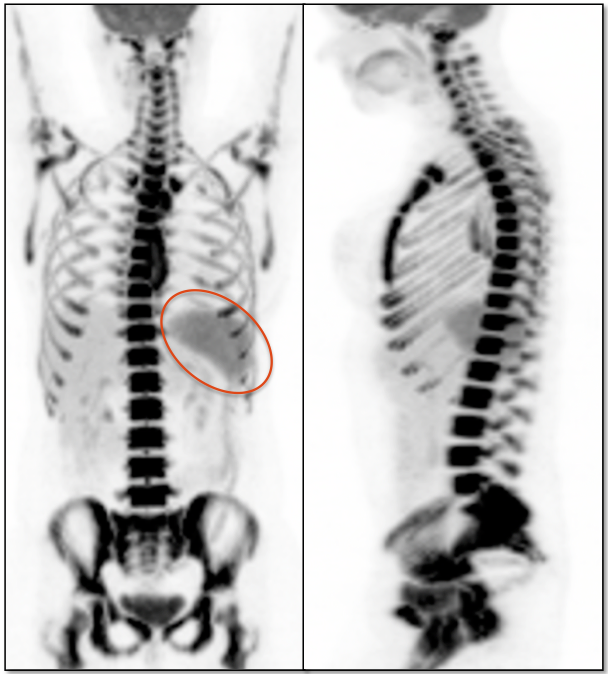

A significant percentage of patients presenting for PET/CT will have recently received chemotherapy and/or colony stimulating factors (CSF), both of which can cause significant diffuse increased metabolic activity of the spleen (and bone marrow, discussed here).

Associated splenomegaly is not uncommon.

• The uptake must be diffuse and not accompanied by lesions on the CT images.

• If uptake is focal, or if the uptake is accompanied by identifiable lesions on the co-registered CT images, malignancy must be strongly suspected.